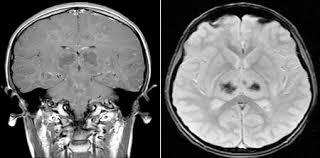

2. Imagenología

1. Por medio de detectores de señales y programas se pueden realizar "cortes" al cerebro o medula espinal de alta resolucion

1. Resonancia magnetica nuclear

1. Se hace posible detectar masas de 2 a 3 mm de longitud

2. Resonancia magentica

1. Es una técnica que sirve para diagnosticar diferentes enfermedades o estados patológicos mediante la obtención de imágenes del cuerpo sin necesidad de utilizar rayos X